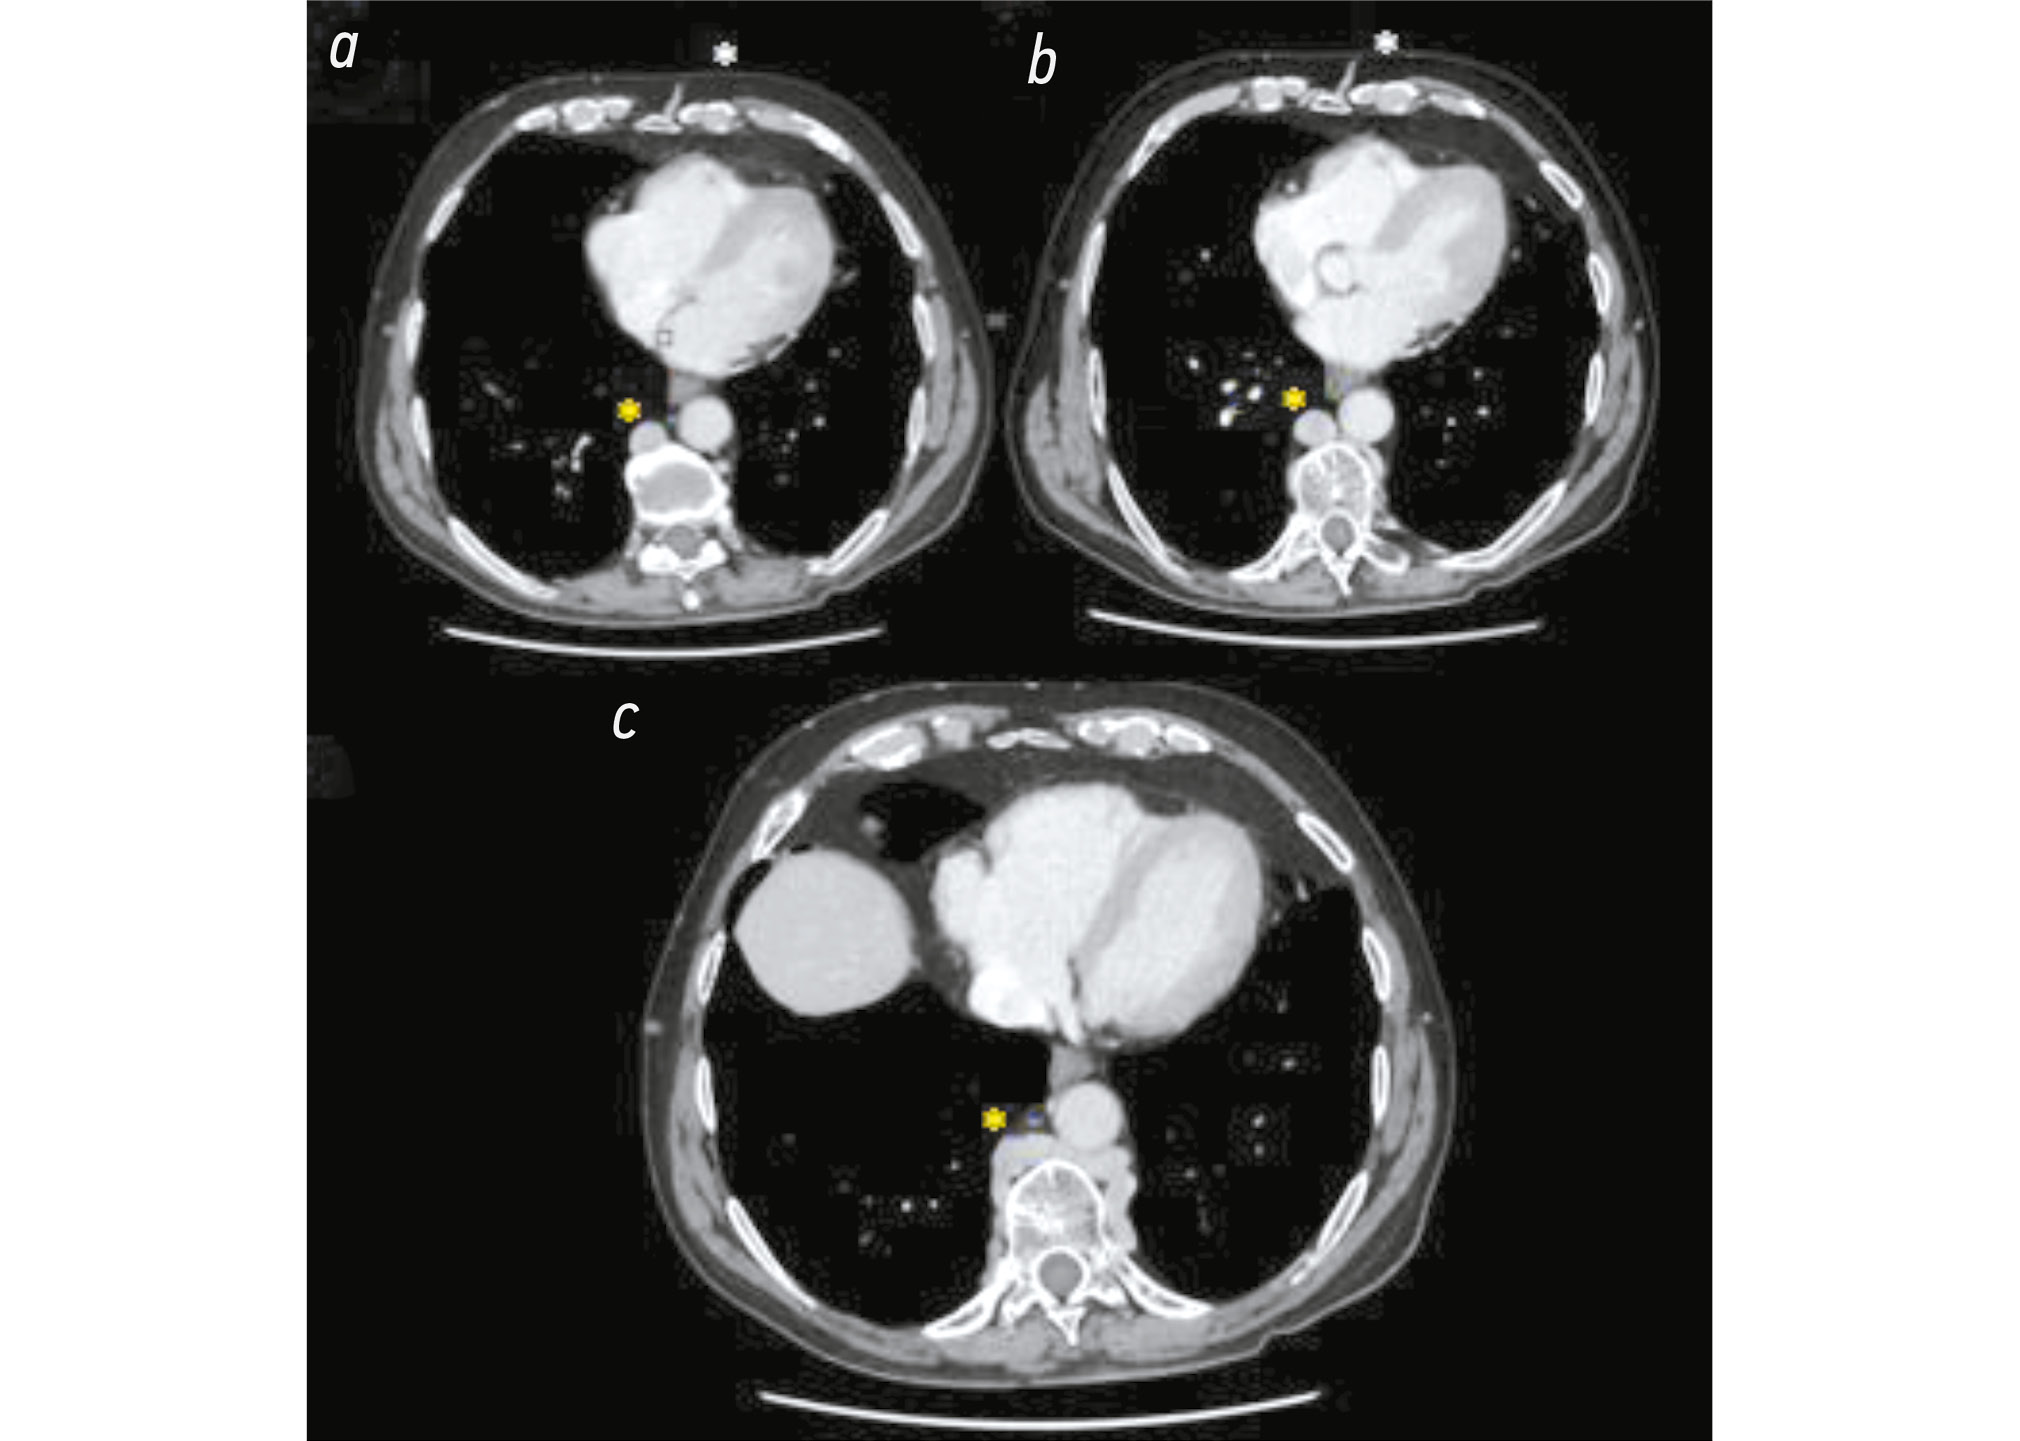

Certain distended azygos and hemiazygos veins received blood from the abdomen. The azygos vein connected with the superior vena cava (SVC) through its arch; however, its dimensions were abnormal. It began from D7 and extended to D10–11, from the confluence of the right renal vein, transhepatic vein, and an aberrant vein (Fig. 3 and Fig. 4).

Fig. 3. Computed tomography images of the coronal section and portal phase of the chest and abdomen: a) The white asterisk indicates the confluence of the giant azygos, hemiazygos, and an aberrant vein. b) Same image at different sections. The yellow asterisk on the right side at the level of the anterior abdominal wall indicates marked collateral vein circles.

Fig. 4. Computed tomography images of the axial section of the chest: the confluence with the hypertrophic azygos and hemiazygos veins is seen in all images at different levels (from upper to lower). In a) and b), the white asterisk marks the confluence of the collateral circles of the abdomen and chest.